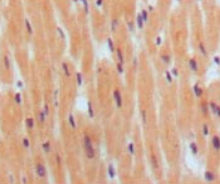

IHC    1/200 - 1/1000